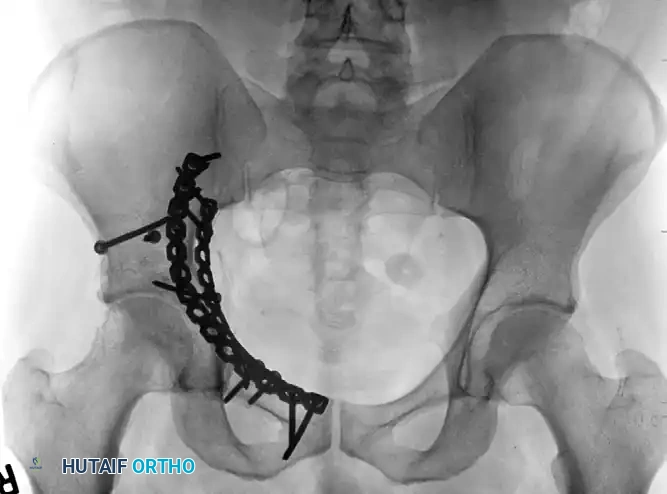

Both-Column Fractures and Indirect Reduction

Both-column fractures represent complete dissociation of the articular surface from the axial skeleton. These complex injuries often require extensive exposures or combined approaches. However, when treated through an ilioinguinal approach, indirect reduction techniques are frequently employed to restore the acetabular dome, with fixation placed on the internal surfaces of the pelvis to buttress the columns.

FIGURE 56-34: Both-column acetabular fracture treated through an ilioinguinal approach with indirect reduction of the acetabulum and fixation placed on the internal surfaces of the pelvis.